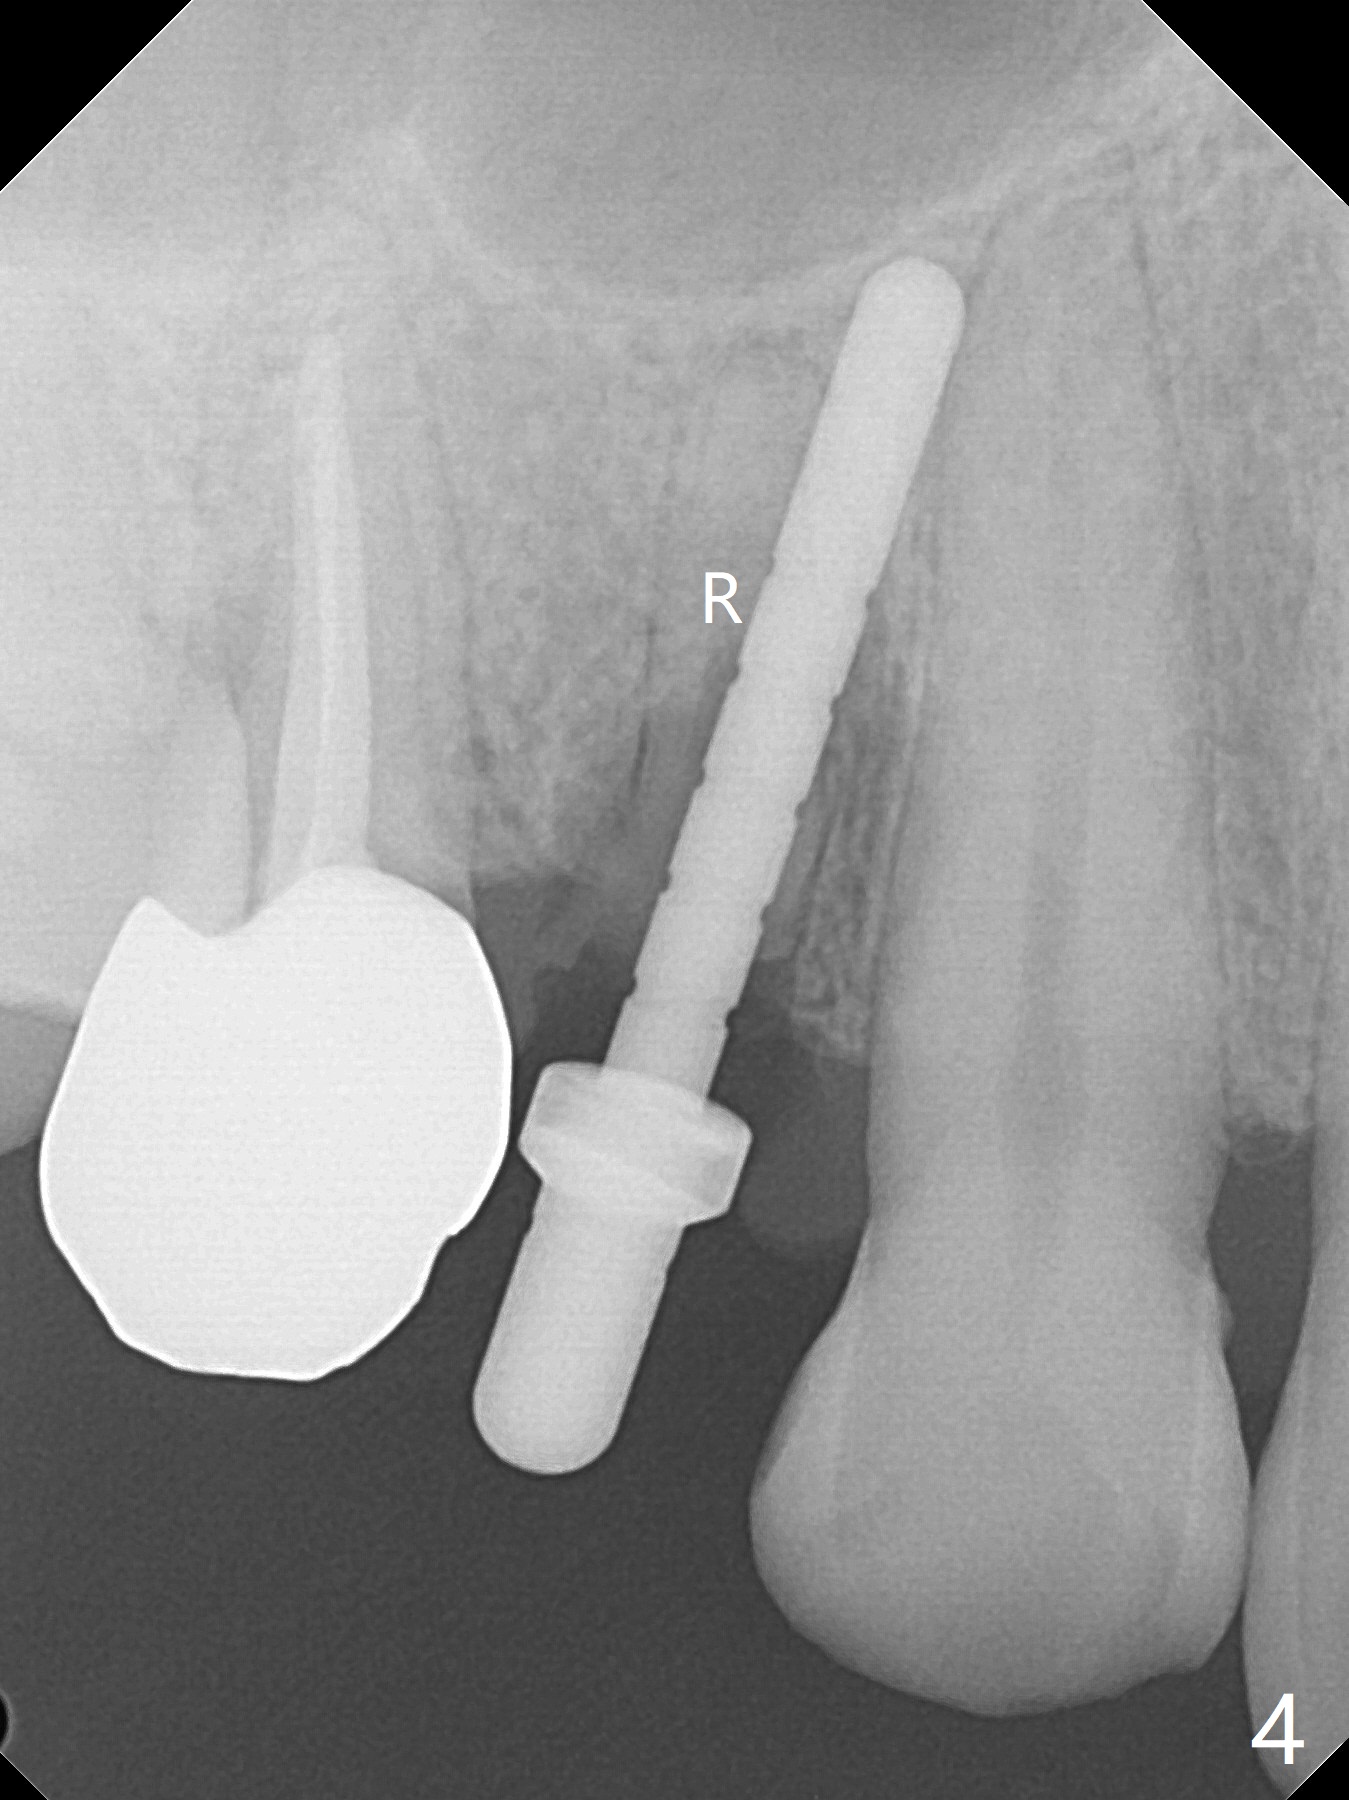

The buccal plate is normal at the tooth #5 (Fig.1) with the loose palatal fragment (Fig.2 P). Extraction leads to root fracture. Sectioning removes the palatal portion of the root and keeps the buccal semilunar piece (Fig.3 *); the mesiopalatal plate is resorbed (P). Initial osteotomy is off (Fig.4 (R: remaining root)). Redirection improves the trajectory (Fig.5). With the 2nd redirection (Fig.6 (4.5 mm tap)), a 4.5x12 mm implant is placed with 50 Ncm and sinus lift (Fig.7 black *); bone graft is placed with emphasis on the palatal defect (white *). As usual, an immediate provisional is fabricated. In fact the abutment may be not completely seated because of contact with the mesial crest. Prepare anesthetic and 5.5 mm profile drill. Take parallel BW or PA. Take occlusal photos to show no buccal or mesiopalatal atrophy. After 5.5 mm profile drill 11 months postop, the abutment has no contact with the mesial crest (Fig.8 <). Since the proximal contact between #3 and 4 is light with food impaction, the provisional at #5 is fabricated with tight distal contact. When the patient returns for final crown cementation (Fig.9), the food impaction is minimal between #3 and 4. The distal black triangle (Fig.10 *) and exposure of the abutment margin (^) are partially related to provisional fabrication and should dissolve over time considering socket shield.